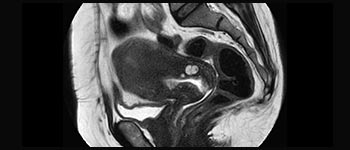

La Sra. Silvia Schiffer, directora y radióloga experta en la clínica Radiologie Schiffer, en Alemania, comparte sus experiencias con el sistema de RM Prodiva 1.5T.

Conozca la opinión de los primeros usuarios de Ingenia Prodiva 1.5T acerca de sus experiencias con el sistema y cómo influye este en su centro de diagnóstico por imagen.